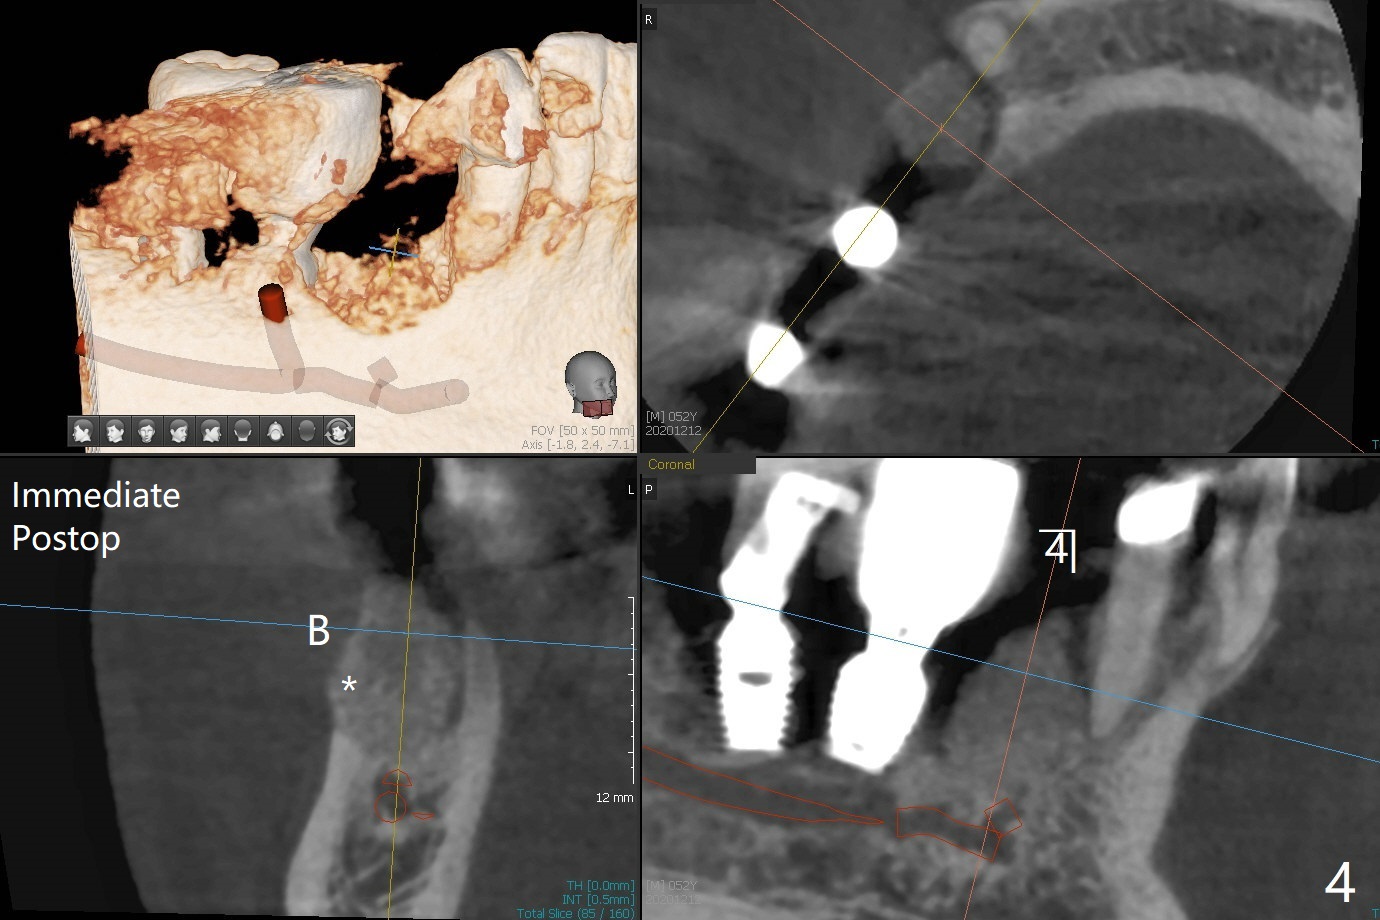

52岁男右下4植体脱落三天回到诊所(图一),植牙创尚未闭锁,顺着开口去除肉芽组织,冲洗,充填皮质骨骨粉(图二,三),颊侧骨板外形恢复(图四,五:*)。重新植入UF植体(5)颊侧还有薄颊侧骨板(图五:>),而6植体周围骨质吸收(图六),植骨好像有希望,植体还在牙槽骨范围,也有利于5植体生存。术后12天伤口愈合(图七)。尽管使用水枪,仍有6植体周围炎,需要治疗(图八)。由于右侧手术,病人不得不用左侧咀嚼,他认为左下4松动,无法挽救。术后3.5个月牙槽嵴和角化龈缩小(图九),需要切开使用导板。术后3.5个月骨粉高度明显下降(图十)。只能植入4x8.5毫米植体(图十一)。